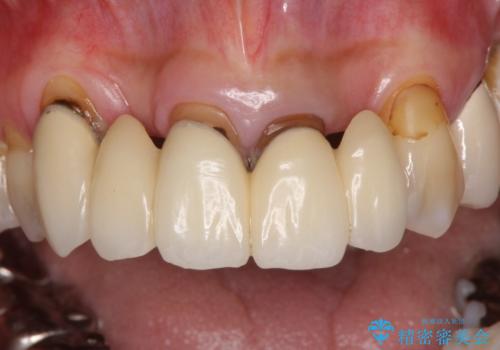

- ブリッジと歯肉の隙間にものが挟まったり空気が抜けたり、歯肉ラインの黒い縁が目立ってしまったりと、前歯のブリッジの作り直しを希望して来院された患者様です。

自然な仕上がりとするため、金属を使用しないオールセラミックブリッジにより補綴治療を行うこととしました。

露出していた歯根や金属の縁が見えてしまい、なかなか口を開けて笑うことができなかったのですが、歯肉の位置に縁を合わせることで自然な仕上がりとなりました。

ブリッジの隙間にものが詰まったり、空気が抜けたりすることも無くなり、話しやすさも改善することができました。